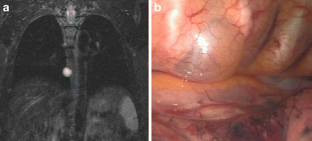

Fig. 4